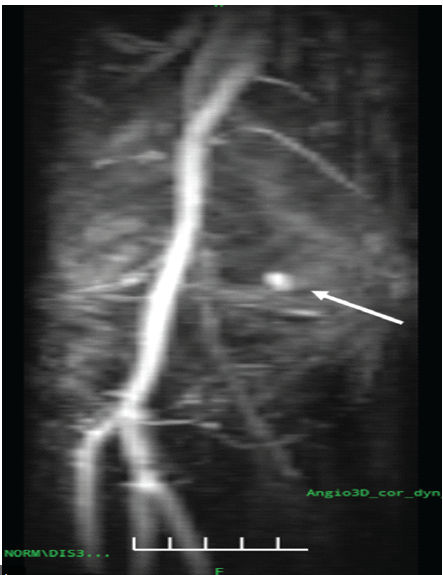

In this case, the pseudoaneurysm measured 10 × 8 mm with a narrow 2.7 mm neck, and Doppler demonstrated the classical “Yin-Yang” sign, confirming turbulent bidirectional flow and suitability for compression therapy. Magnetic resonance angiography subsequently confirmed a pseudoaneurysm arising from the superior medial genicular artery adjacent to the joint capsule (Fig. 3).

Figure 3: Magnetic resonance angiography of the right knee demonstrating a saccular pseudoaneurysm arising from the superior medial genicular artery adjacent to the joint capsule, with preserved popliteal artery flow (white arrow).